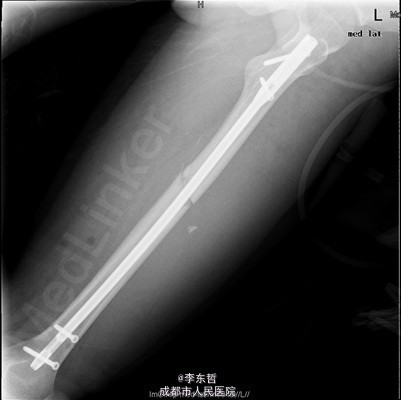

患者男,19岁,因“车祸伤致左下肢活动障碍5小时”入院。5小时前,患者骑电瓶车不慎与另一电动摩托车相撞倒地,当即感左大腿疼痛,畸形,活动受限,右小腿皮肤挫伤、出血,无头晕头痛,无大小便失禁。就诊于当地医院,检查提示:左股骨中段横行骨折。急诊行左大腿夹板外固定,右小腿清创缝合术,术后未进一步治疗,患者为进一步诊治来我院,急诊以左股骨中段骨折收入我科。 自患病以来,患者一般情况尚可,精神睡眠可,小便正常,大便未解。

查体:左大腿夹板固定,肿胀明显,短缩、畸形,右小腿内前方可见一长约5cm创口,已缝合,内植引流条一根,无明显肿胀。左大腿中段环周压痛,可扪及骨折断端,右小腿无明显压痛,双下肢感觉正常。左膝及髋关节明显活动受限,左足背及右下肢活动正常。 辅查:外院X片示:左侧股骨中上段可见骨质断裂征象,断端分离、错位、重叠,周围软组织肿胀;双侧胫腓骨、左膝关节各骨及左踝关节未见确切骨质断裂征象。

初步诊断:1、左股骨中段横行骨折,2、右小腿皮肤软组织裂伤清创缝合术后。 诊疗计划:1、向患者及家属交待病情及注意事项。2、向上级医生汇报患者病情。3、完善术前相关检查。4、给予皮肤牵引、抬高患肢等对症处理。5、拟进一步手术治疗。6、密切观察病情变化,根据病情及时处理